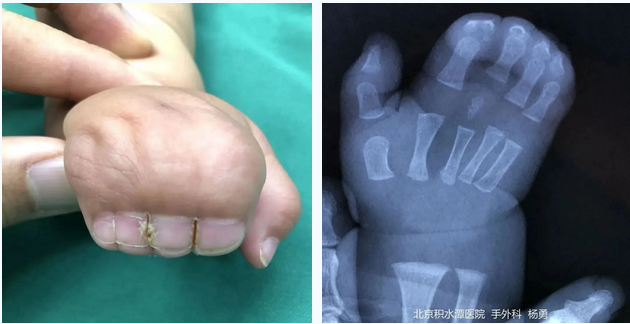

图|我院手外科接诊的手部畸形患儿

新生儿出生后手部虎口、示中指、中环指和环小指指蹼高于正常高度,表现为手指不同程度的并连,即可诊断为并指。

临床两指并指相对多见,三个或更多的手指并在一起相对少见。综合征畸形多表现为多个手指并指,如Poland综合征、Apert综合征。

问:并指畸形分为哪几种类型?

并指畸形的分型主要依据并指的范围、程度和累及结构,可有以下几种分型。

不完全并指:皮肤相连未及手指全长。

完全并指:并指的范围累及手指全长。

皮肤性并指:仅为皮肤相连。

骨性并指:手指之间存在指骨融合。

复杂并指:表现为并指多指或合并其他手指畸形等更为复杂的情况。